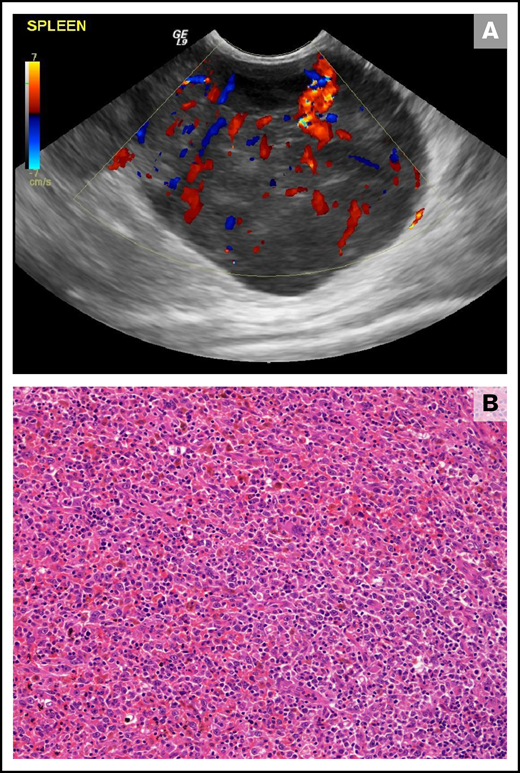

Canine HS is a malignancy that is broadly classified as either localized or disseminated depending upon disease extent.85 Canine HS usually occurs in adults of various breeds, with Bernese mountain dogs, retrievers, rottweilers, and miniature schnauzers being predisposed.85,87,88 Primary disease can be localized to the periarticular tissue, lymph node, skin, lung, bone marrow, and spleen (Figure 3), with other sites less frequently affected, whereas disseminated disease involves multiple sites and organs.85,87 Clinical signs may be vague, such as weight loss or lethargy, or may be specific to infiltrated tissue, such as joint pain and swelling.85,87 Canine HS is derived from interstitial dendritic cells that express CD1a, CD11c/CD18, and IBA1.85,86 Although E-cadherin expression is not classically associated with HS, E-cadherin+ cutaneous HS has been described.85,89 Localized HSs are variably infiltrated by immune T cells, with increased T-cell density being associated with favorable outcomes.90 Genetic analyses of canine HS have revealed association between mutations affecting PTEN, PTPN11, and KRAS with activation of MAPK pathway signaling.91-93 Hemophagocytic HS follows an aggressive course; dogs frequently present with Coombs− anemias, often accompanied by thrombocytopenia, hyperbilirubinemia, hypoalbuminemia, and hypocholesterolemia.85,94 Immunophenotypically, hemophagocytic HS expresses markers of the macrophage lineage (CD11d/CD18+, CD1a low).85,94 Dendritic cell leukemia is rarely reported in dogs and manifests as marked leukocytosis with potential for effacement of pulmonary, splenic, and hepatic tissue.85,95

Splenic HS in a 10-year-old female neutered cross-breed dog. (A) Ultrasonographic still of a large (maximum diameter, 59 mm) well-vascularized (as demonstrated by Doppler color flow) mass lesion of mixed echogenicity within the tail of the spleen. (B) Histopathology of the splenic mass revealed a poorly encapsulated neoplasm showing both round and spindle morphologies of large tumor cells forming sheets and streams. Diagnosis of HS was confirmed using immunohistochemical stains (not shown; hematoxylin and eosin stain; ×20 objective).